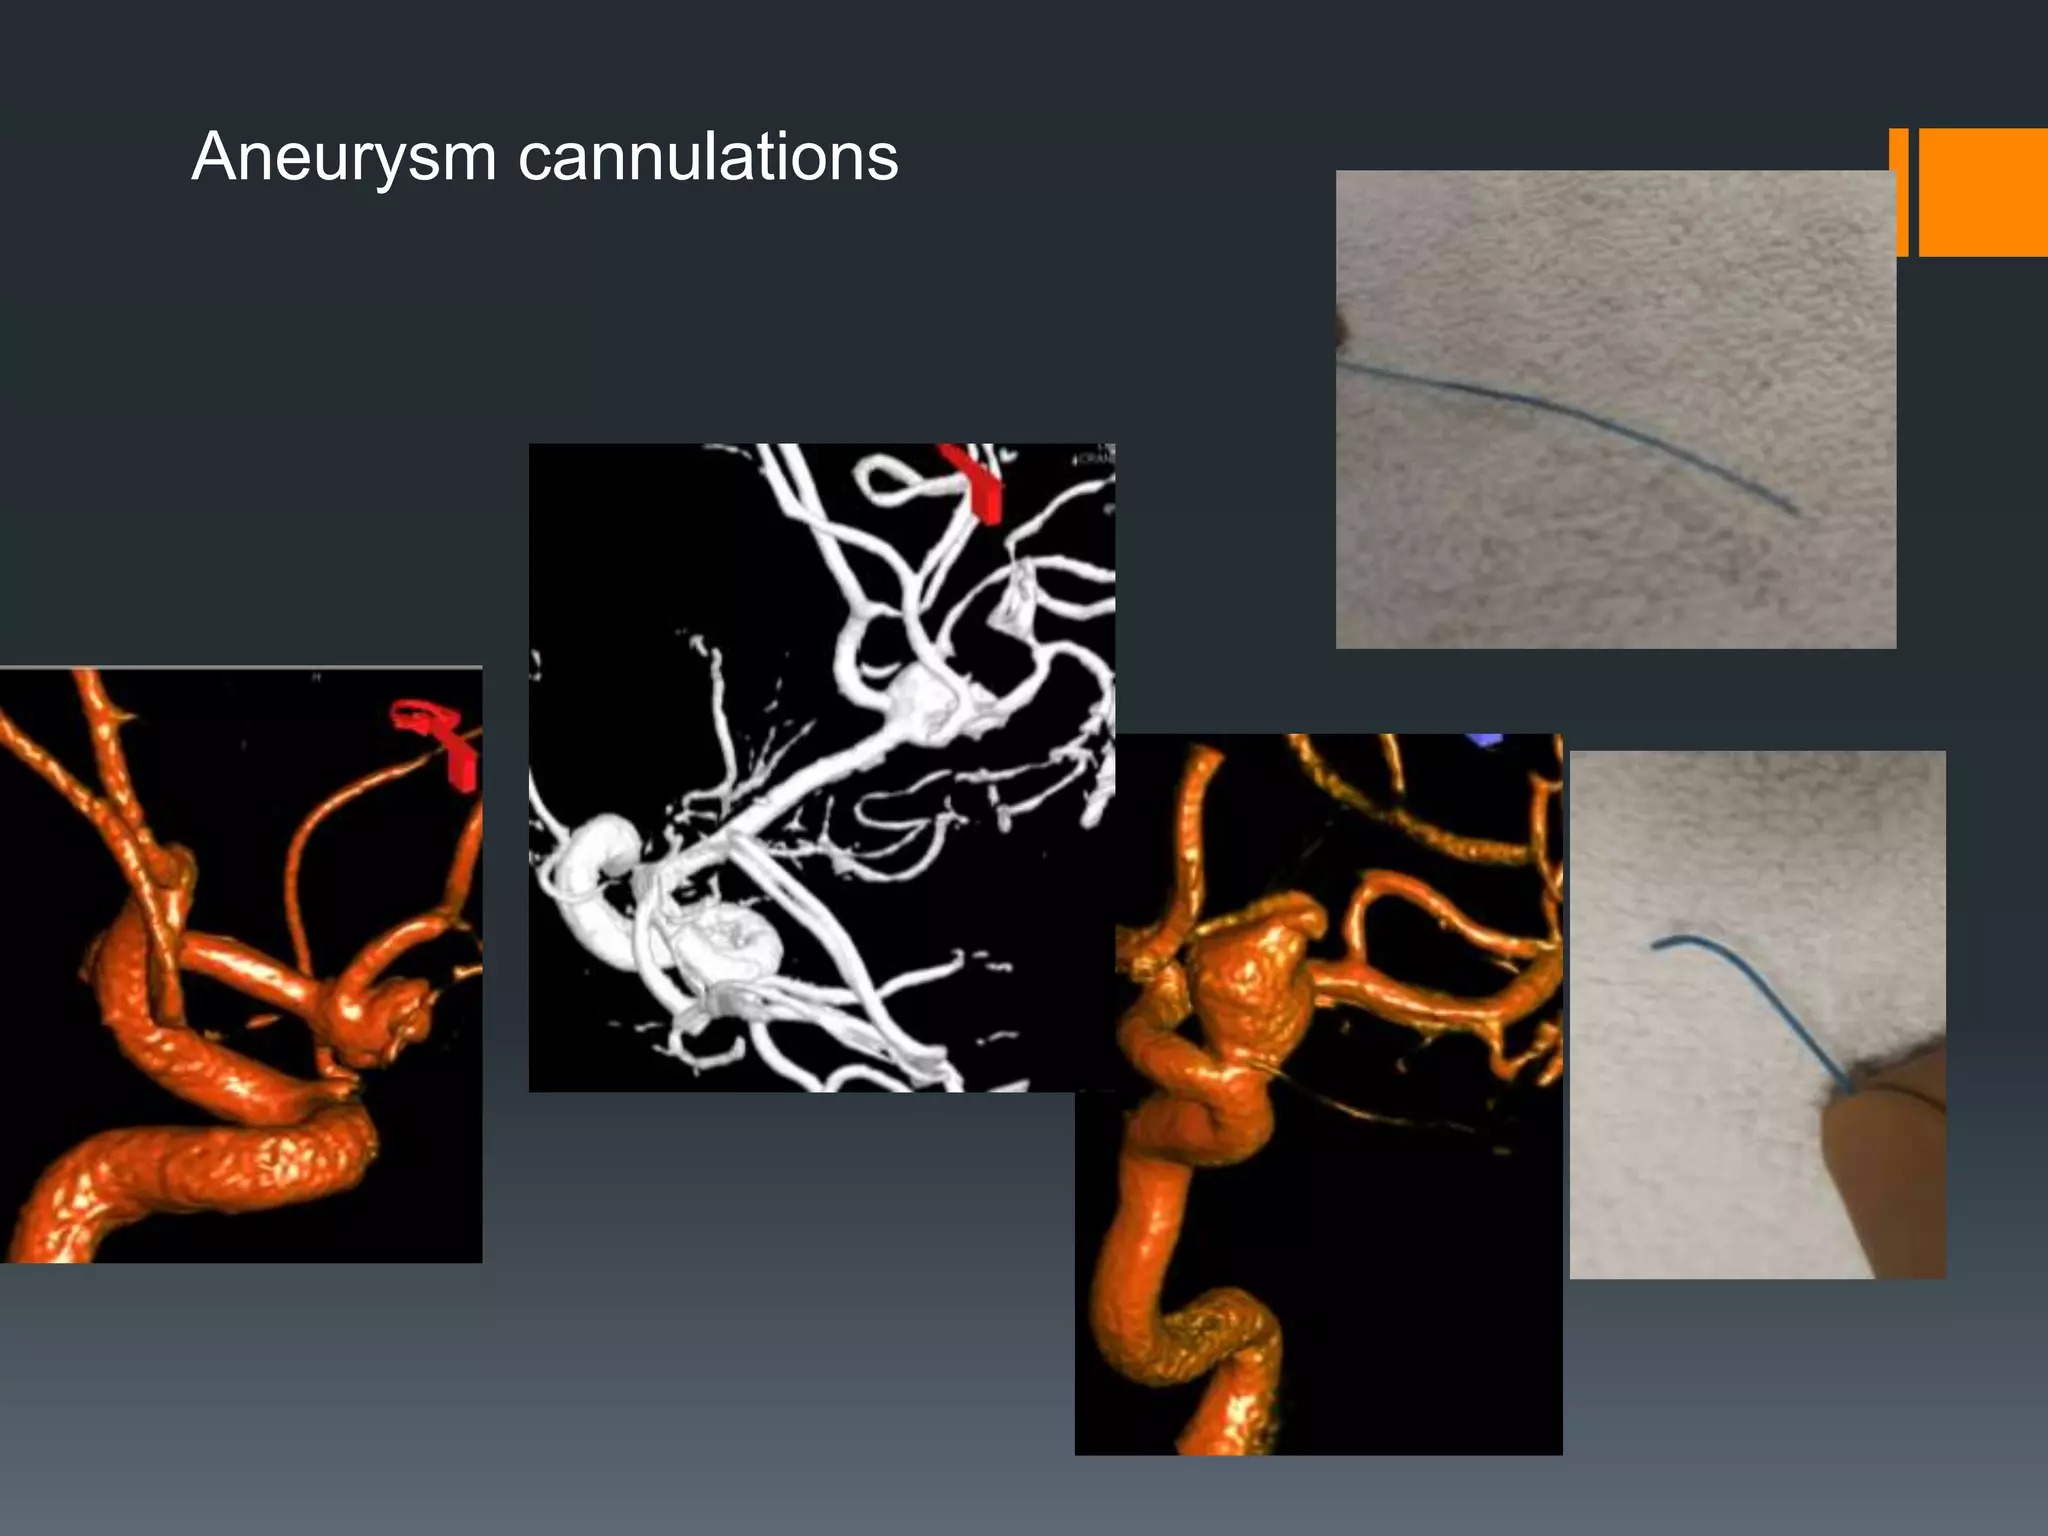

This document discusses tricks and techniques for difficult cannulations during neurointerventional procedures. It outlines strategies for accessing the aortic arch, internal carotid artery (ICA), and areas distal to aneurysms. Long sheaths, distal access catheters, and co-axial techniques are presented as options that have improved cannulation success. Guidance on sheath and catheter selection is provided for different vessel paths. The importance of catheter placement as high as possible in the ICA is emphasized. Reverse curve cannulations are also mentioned. Overall, the document stresses that careful cannulation is critical for procedural success and different strategies may be needed depending on the vessel target.